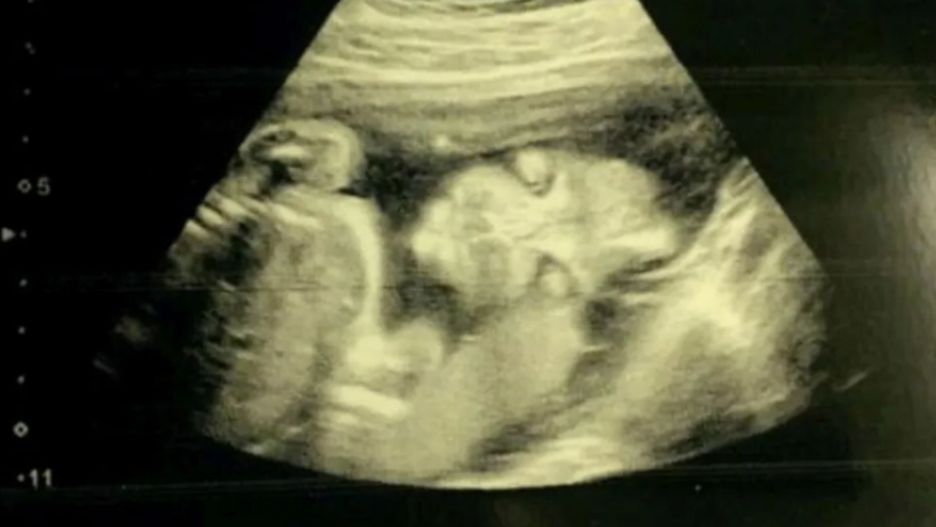

Moment, gdy podczas wykonywanego USG na ekranie komputera pojawia się dziecko, jest jednym z najlepszych i najbardziej niezwykłych chwil w życiu. Jednak nie dla wszystkich. Pewna kobieta była przerażona, gdy podczas badania zobaczyła twarz swojej córki.

Była przerażona, gdy ujrzała zarys zgarbionego dziecka z dużymi oczami i wydłużonymi palcami przypominającymi szpony. Jej przyszła córeczka nie chciała się obrócić bokiem i jedyne, co mogła zobaczyć, to portret en face. Dziecko było cały czas zwrócone na wprost i nie dało się go przekonać, by odwróciło się na bok.

Jade przyznała, że gdy po raz pierwszy zobaczyła twarz swojej córki, nazwała ją "demonicznym dzieckiem". Opublikowała zdjęcie mediach społecznościowych, gdzie wielu internautów żartowało z wyglądu dziecka.

Takie zdjęcia podczas USG się zdarzają i nie są powodem do niepokoju. Jednak charakter dziewczynki, zdaniem mamy, jest z pewnością demoniczny.